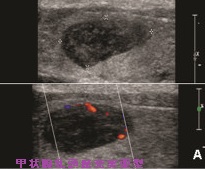

甲状腺乳頭癌充実亜型 超音波(エコー)所見

甲状腺乳頭癌充実亜型(SVPTC)の超音波(エコー)所見は多彩で、腺腫様結節に見えるものから、濾胞型乳頭癌の様なものまであります。そもそも、ヨード(ヨウ素)欠乏のため乳頭状構造にならなかっただけと考えれば、通常の甲状腺乳頭癌と差が無いのかもしれません。(写真;Cancer Cytopathol. 2015 Feb;123(2):71-81.)

- 術前超音波検査で乳頭癌疑いが74%、濾胞癌疑いが11%